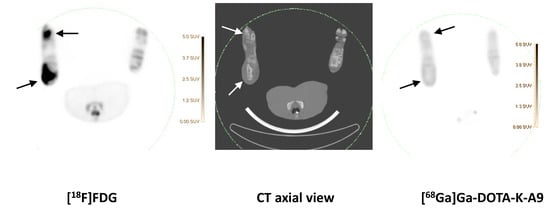

While previous evaluation in murine subcutaneous S. aureus infections showed uptake of [68Ga]Ga-DOTA-K-A9 [9,14], we saw no increased tracer activity of the two S. aureus phage displayed selected peptides, [68Ga]Ga-DOTA-K-A9 (Figure 1) and [68Ga]Ga-GSG-KA-11 (Figure 2) in 9 and 5, respectively, porcine OM lesions. Figure 3 shows the bio-distribution of the peptides in pigs. Both peptides were excreted by the liver and kidneys.

[18F]FDG (left) and Ga-DOTA-K-A9 (right) accumulation is shown in an OM lesion in the right calcaneus and distal II metatarsus of pig 4 (indicated by arrows). The lesions show sequester formation and lysis of the cortical bone on CT in the axial view (middle). Comparable SUV scales are shown to the right of the PET images.